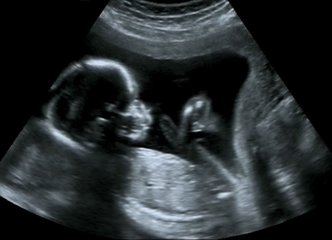

医生在做b超时会在屏幕前仔细研究半天,通过b超究竟能看到什么?

怀孕5个月后,通过b超就可以看到发育比较健全的胎儿了,如脸、五官、躯干、四肢,还有连接母体的脐带和胎盘等。